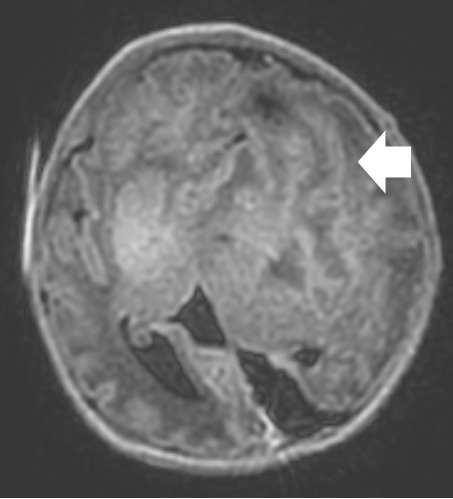

A repeat MRI on day-of-life 1 revealed multiple intracranial anomalies including extensive polymicrogyria of the left cerebral hemisphere, polymicrogyria in the right frontal lobe, incomplete development of the left lateral ventricle, and a gray matter lined cerebrospinal fluid cleft in the left posterior-frontal and parietal regions communicating with the rudimentary left lateral ventricle (Figures 5-7). The dysplastic left cerebral hemisphere exerted a mass effect on the rudimentary left lateral ventricle with a left-to-right midline shift measuring approximately 6 mm at the level of the foramen of Monroe. There was evidence of partial fusion of the frontal lobes. In summary, the first postnatal MRI confirmed that rather than a growing neoplasm, Twin A had extensive intracranial developmental anomalies, including a dysplastic left cerebral cortex, schizencephaly, and hypoplasia or absence of multiple midline structures.